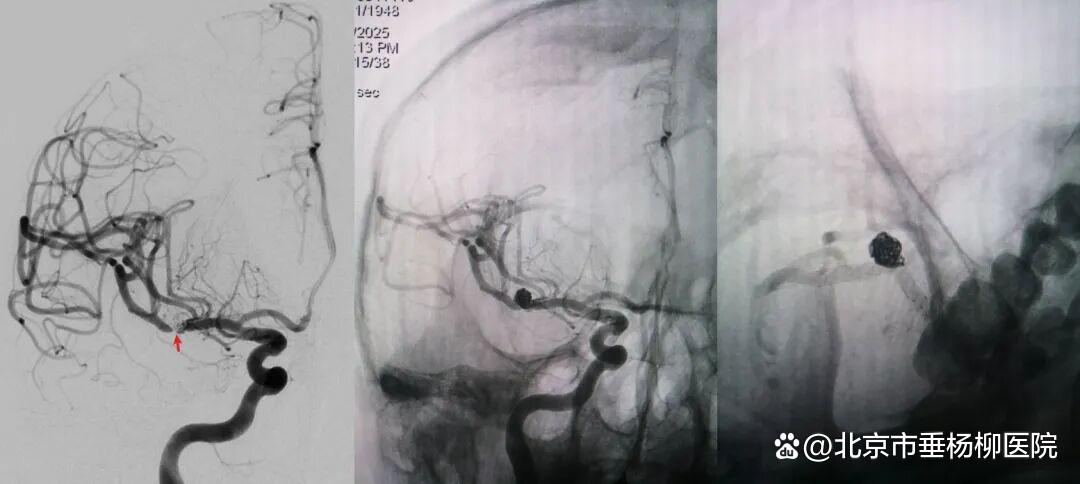

病例二为58岁女性患者。因“突发剧烈头痛伴呕吐3小时”就诊于清华大学附属垂杨柳医院急诊科,行头颅CT检查提示蛛网膜下腔出血。患者嗜睡,频繁呕吐,不排除颅内再出血。为争分夺秒抢救患者生命,神经外科脑血管病介入团队紧急为患者实施了DSA,显示左侧大脑中动脉分叉处宽颈动脉瘤,主要累及下干。术中采取双微导管技术,于动脉瘤内填塞弹簧圈,并置入一枚支架保证致密栓塞和下干分支血管的通畅。成功“拆弹”,化险为夷,患者恢复过程顺利,出院时无神经功能缺损。

▲术前DSA显示左侧大脑中动脉分叉宽颈动脉瘤可见子瘤,主要累及下干

▲术后DSA显示动脉瘤致密栓塞,载瘤动脉通畅